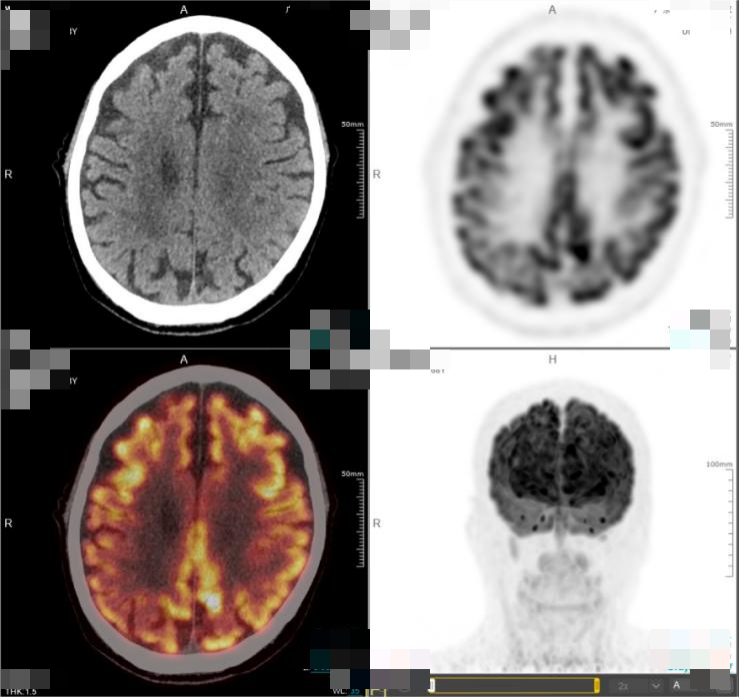

· 2025年5月,外院进行的头颅MRI检查结果显示,该患者的肿瘤再次进展。基于患者目前的疾病情况,中心医生先对其行全脑放疗,使用BTK抑制剂口服治疗,并且同步准备CAR-T细胞培养。此外,该患者还接受了氟达拉滨联合环磷酰胺方案进行预处理治疗,并于6月26日成功回输CD19 CAR-T细胞。在放疗后,患者的头颅MRI提示颅内病灶较前明显减少、减小。而CAR-T细胞治疗后50天复查PET-CT显示,患者的颅内肿瘤病灶已完全消失,达到完全代谢缓解(CMR)

图1.png图1. 患者的头颅MRI对比图